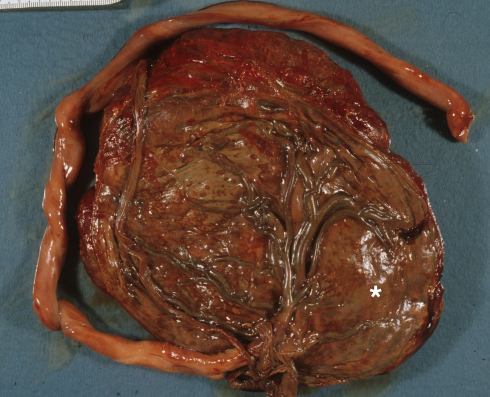

Fig 6b When the placenta in Fig 28a was sectioned, the margins could be seen to be a circummarginal old Breus mole with a second more acute Breus mole reaching from the margin to the center of the placenta (*).

Fig 28b: When the placenta in Fig 28a was sectioned, the margins could be seen to be a circummarginal old Breus mole with a second more acute Breus mole reaching from the margin to the center of the placenta (*).